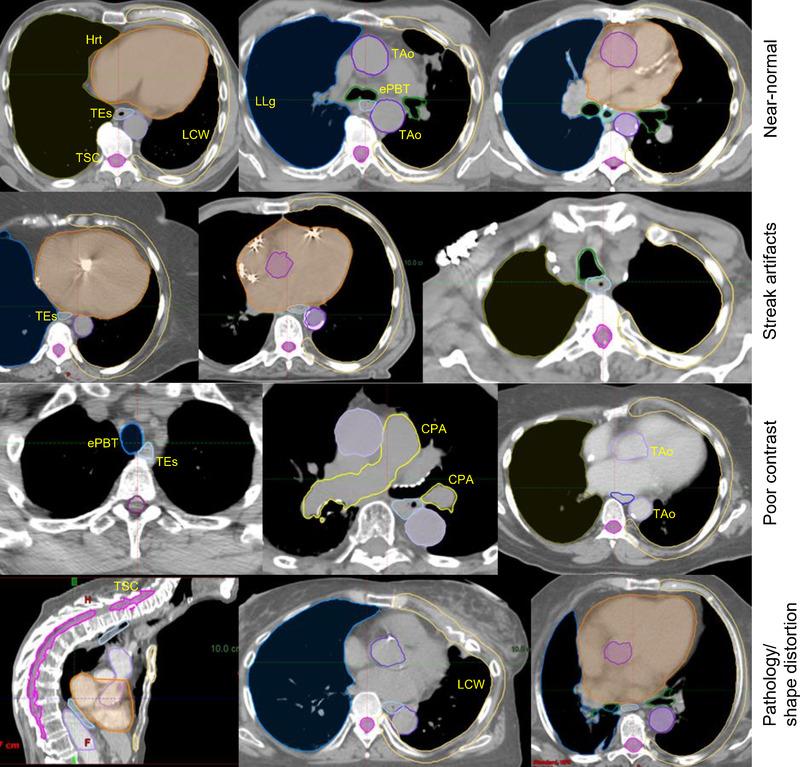

The HI system was tested on 26 organs in neck and thorax body regions on CT images obtained prospectively from 464 patients in a study involving four RT centers. Data sets from one separate independent institution involving 125 patients were employed in training/model building for each of the two body regions, whereas 104 and 110 data sets from the 4 RT centers were utilized for testing on neck and thorax, respectively. In the testing data sets, 83% of the images had limitations such as streak artifacts, poor contrast, shape distortion, pathology, or implants. The contours output by the HI system were compared to contours drawn in clinical practice at the four RT centers by utilizing an independently established ground-truth set of contours as reference. Three sets of measures were employed: accuracy via Dice coefficient (DC) and Hausdorff boundary distance (HD), subjective clinical acceptability via a blinded reader study, and efficiency by measuring human time saved in contouring by the HI system. Overall, the HI system achieved a mean DC of 0.78 and 0.87 and a mean HD of 2.22 and 4.53 mm for neck and thorax, respectively. It significantly outperformed clinical contouring in accuracy and saved overall 70% of human time over clinical contouring time, whereas acceptability scores varied significantly from site to site for both auto-contours and clinically drawn contours.

在涉及四个 RT 中心的前瞻性前瞻性研究中,对 464 名患者的 CT 图像中颈部和胸部区域的 26 个器官进行了 HI 系统测试。两个身体区域的每个都使用来自一个单独的独立机构的 125 个患者的数据集进行培训/模型构建,而来自 4 个 RT 中心的 104 个和 110 个数据集分别用于颈部和胸部的测试。在测试数据集中,83%的图像存在条纹伪影、对比度差、形状变形、病变或植入物等局限性。HI 系统输出的轮廓与四个 RT 中心的临床实践中绘制的轮廓进行了比较,使用独立建立的轮廓真值集作为参考。采用了三组度量标准:通过 Dice 系数(DC)和 Hausdorff 边界距离(HD)进行准确性,通过盲法读者研究进行主观临床可接受性,以及通过 HI 系统节省的人类描绘时间进行效率。总体而言,HI 系统在颈部和胸部的平均 DC 分别为 0.78 和 0.87,平均 HD 分别为 2.22 和 4.53 毫米。它在准确性方面明显优于临床描绘,在整体上比临床描绘节省了 70%的时间,而自动轮廓和临床绘制的轮廓的可接受性评分因站点而异。